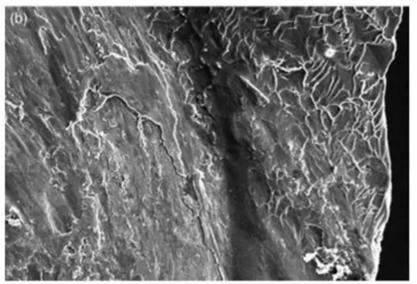

要深入了解器械斷裂的發(fā)生機(jī)制,就必須要在足夠的放大倍數(shù)下觀察斷裂面 (如上圖),也就是所謂的顯微斷口研究 (fractographic study)。這些為數(shù)不多的實驗大部分是針對機(jī)用鎳鈦銼。系統(tǒng)來說,斷裂機(jī)制主要分為剪切/扭矩破壞(shear/torsional failure)和疲勞破壞(fatigue failure) (Cheung et al. 2005)。

這是上圖B區(qū)域的放大圖像,顯示了剪切失敗的斷面特征: 斷面四周為不規(guī)則的韌窩(dimples)(圖片右側(cè))和中心共軸的磨損印記(concentric abrasion marks)(圖片左側(cè))

當(dāng)銼的尖端被卡緊的同時上段仍持續(xù)扭轉(zhuǎn),所產(chǎn)生的應(yīng)力超出材料自身的極限抗剪強度(ultimate shear strength)的那一刻,剪切破壞隨即發(fā)生。其斷口特征主要為(Cheung 2007)

1. 中心共軸磨損(centric concentric abrasion): 這是由于在發(fā)生折斷時,斷面兩端互相摩擦所造成的印記;

微觀下的韌窩形態(tài)

2.偏斜的韌窩 (skewed dimple):所有類似鎳鈦金屬,具有延展性(ductile)的材料內(nèi)部都固有大量的孔洞(void)。當(dāng)受到外力時,孔洞體積會不斷增加直到位于孔洞間的完整材料由于過度拉伸而破裂,這就是韌窩的產(chǎn)生機(jī)制。當(dāng)材料受到的是由扭轉(zhuǎn)所產(chǎn)生的剪切應(yīng)力,其韌窩圖案都是偏斜的。